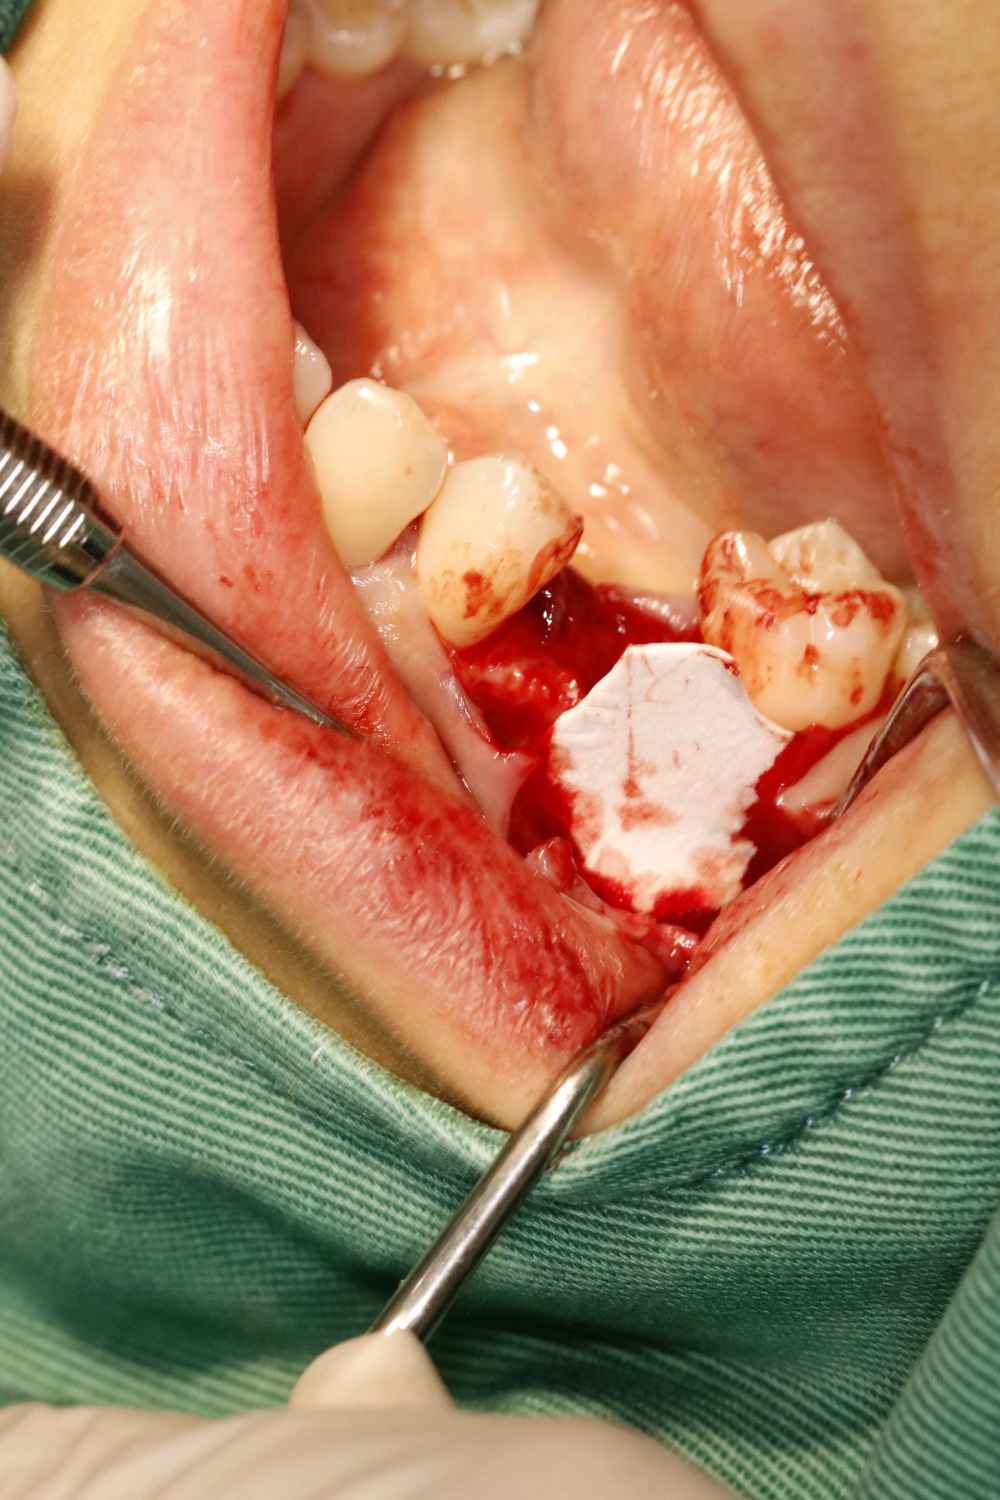

患者女三十岁,35畸形中央尖折断,根尖周炎症感染,导致牙根发育停止,根尖口呈喇叭口状。拔出后搔刮牙槽窝,颊侧骨壁吸收,植入骨粉骨膜。定期复查,将近半年见骨密度良好,骨量充足的条件下,行种植手术。植入3I 4/3*11.5mm的种植体。二期三期如期进行,与今日戴牙,患者满意。

术后